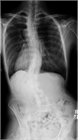

1. 若年者での脊柱変形は、先天性側弯症や思春期に発症する特発性側弯症が多く、通常痛みや機能障害を伴わない場合が多いが、成長に伴い変形が増悪する可能性が高いので見過ごしてはならない。特に特発性側弯症は、思春期の急速な成長期に進行するリスクが高いため、早期発見と適切な介入が重要である。